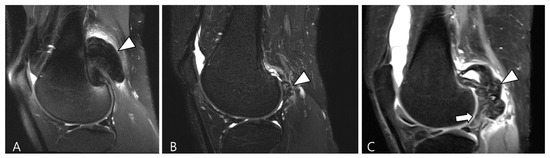

4. MRI Findings for D-TSGCT on Follow-Up MRI

4.2. Checklists on Follow-Up MRI for D-TSGCT